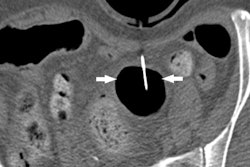

So far, most of the studies about 3D printing have focused on using the technology to make patient-centered structures, such as models of organs or implants. But a group from Brigham and Women's Hospital has shown that 3D printing also can be used to craft customized tools that radiologists can use in interventional studies.

Brigham researchers wanted to modify F-Spoon, a commercially available paddle for CT-guided interventional procedures. So they scanned the device, made changes to the digital file using computer-aided design software, and then output the modified paddle using a 3D printer.

How well did the 3D-printed paddle work? You'll have to click here to find out, for a new article in our Advanced Visualization Community.